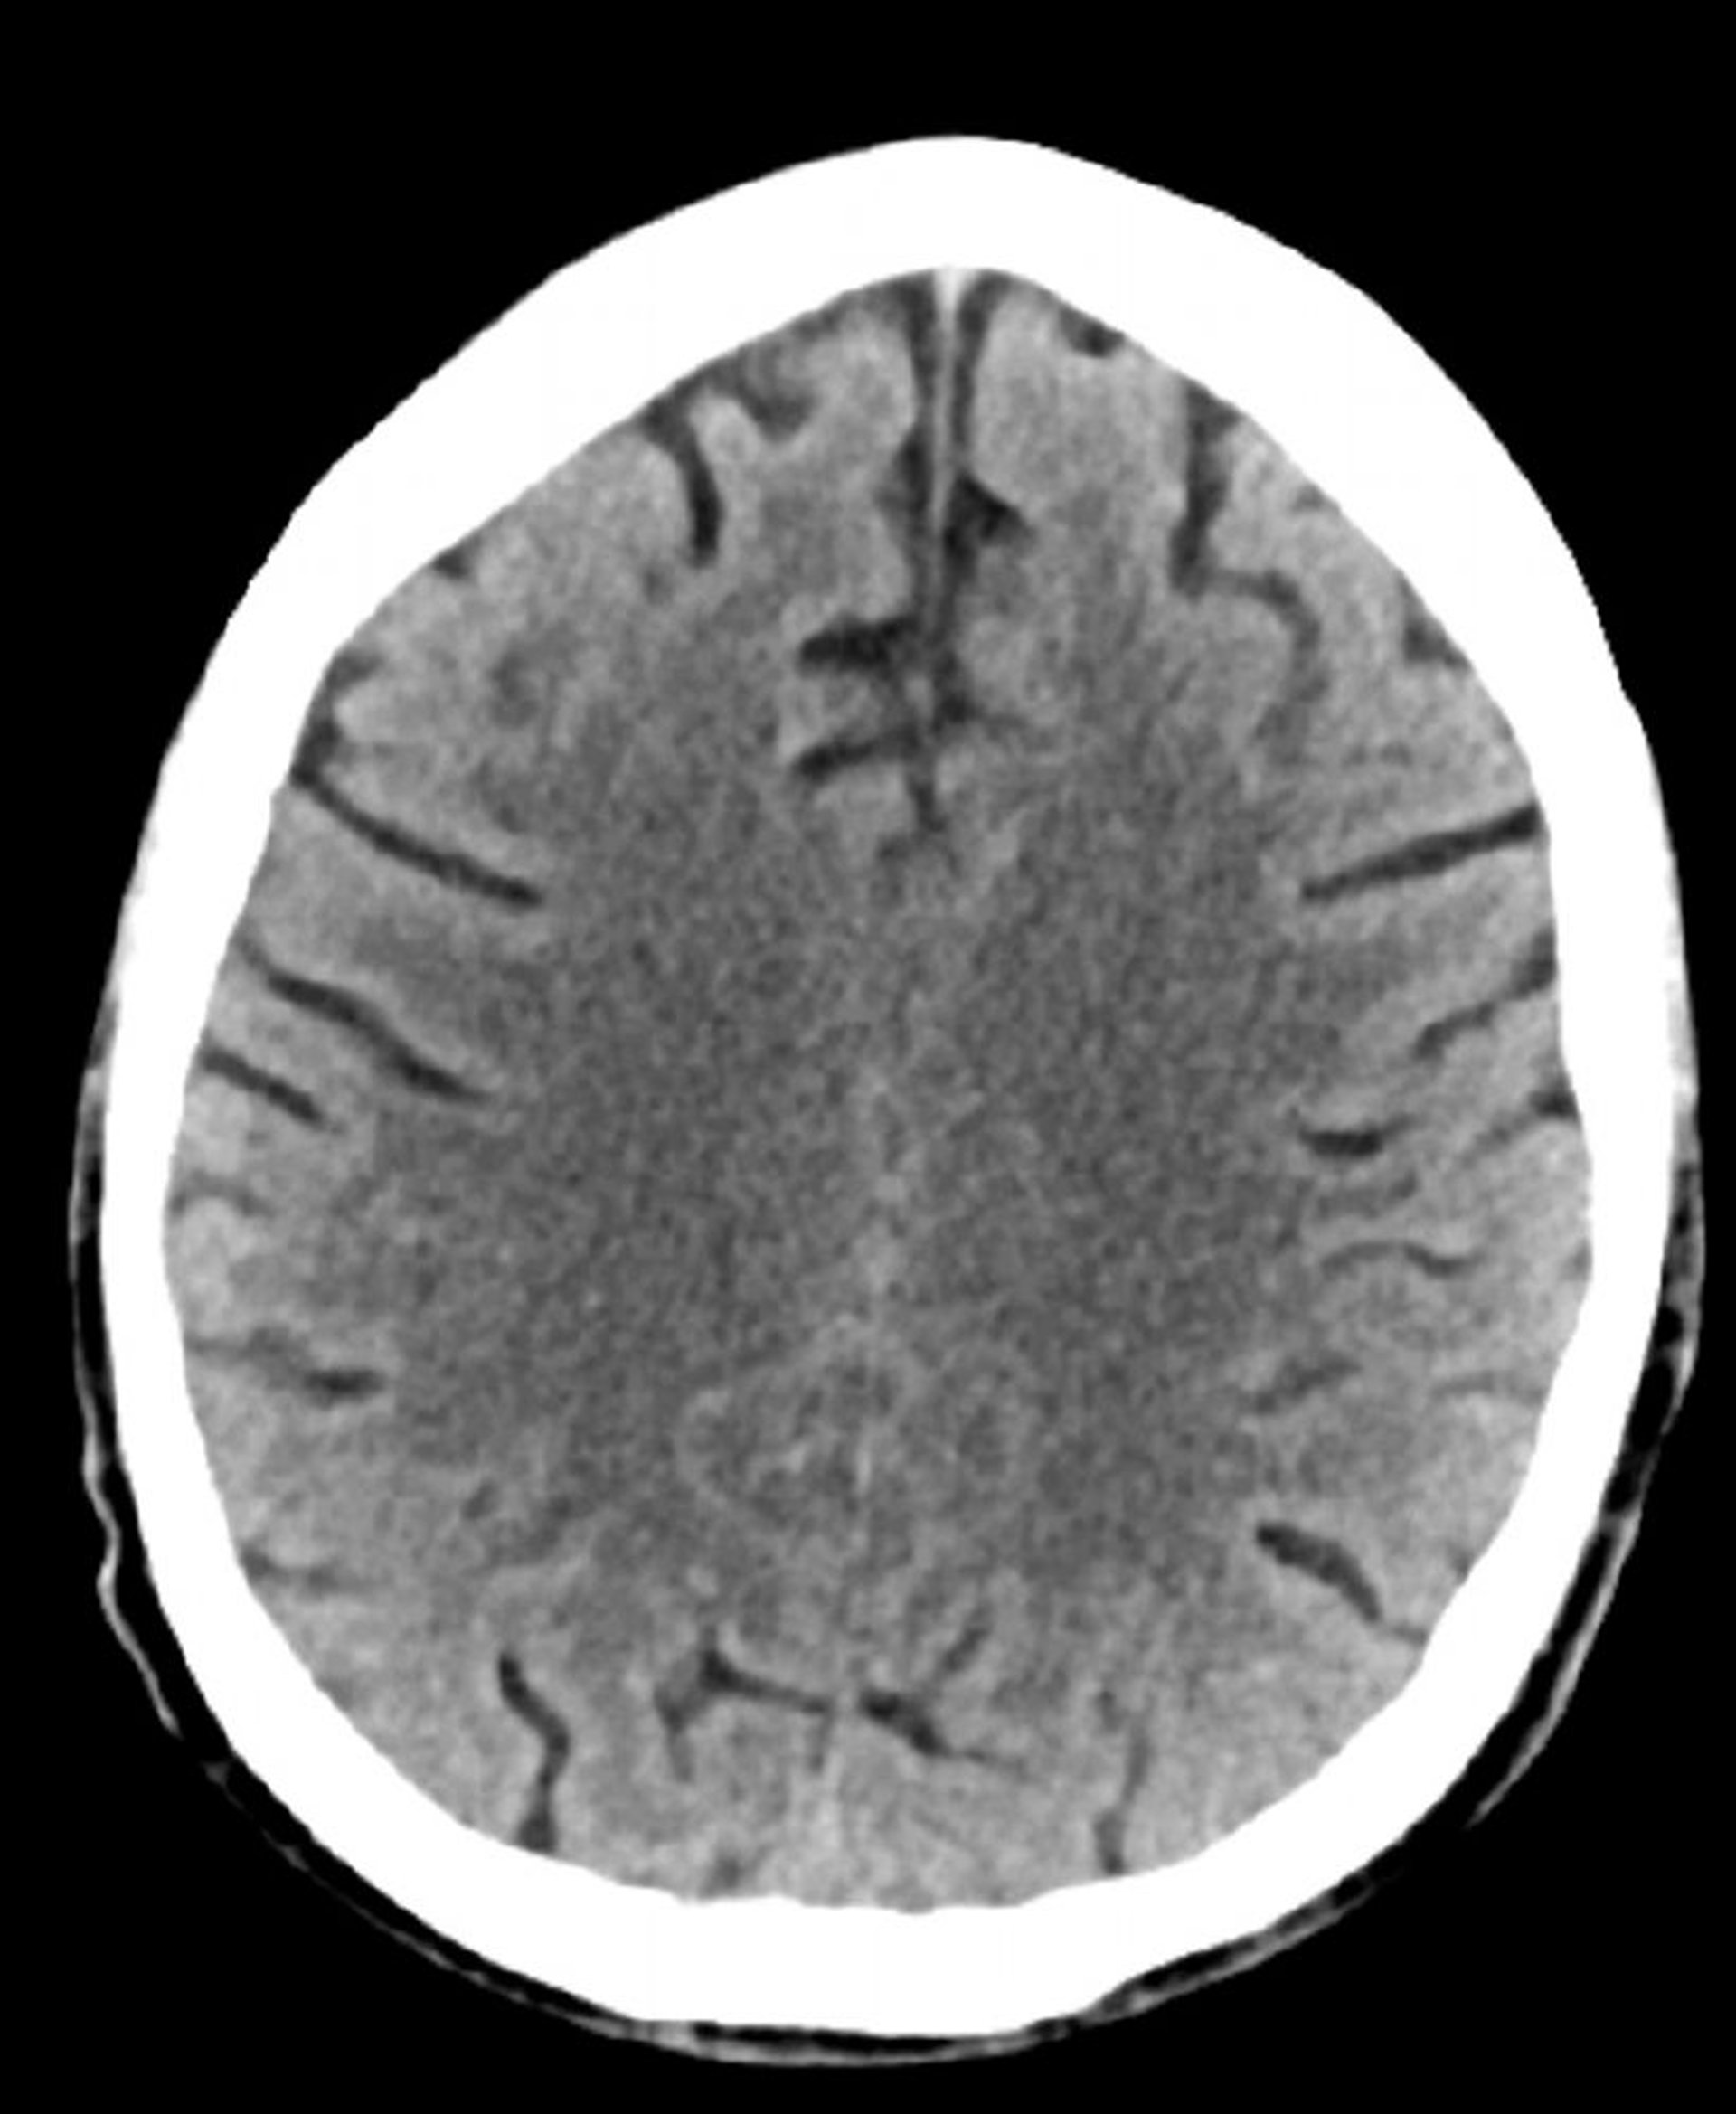

Tomodensitométrie normale de la tête (adulte, 74 ans) – Diapositive 2

Cette image est une TDM normale de la tête d'un adulte âgé de 74 ans. Par rapport à la TDM normale de la tête d'un patient de 30 ans, les sillons sont plus grands. Ces signes sont normaux dans ce groupe d'âge.